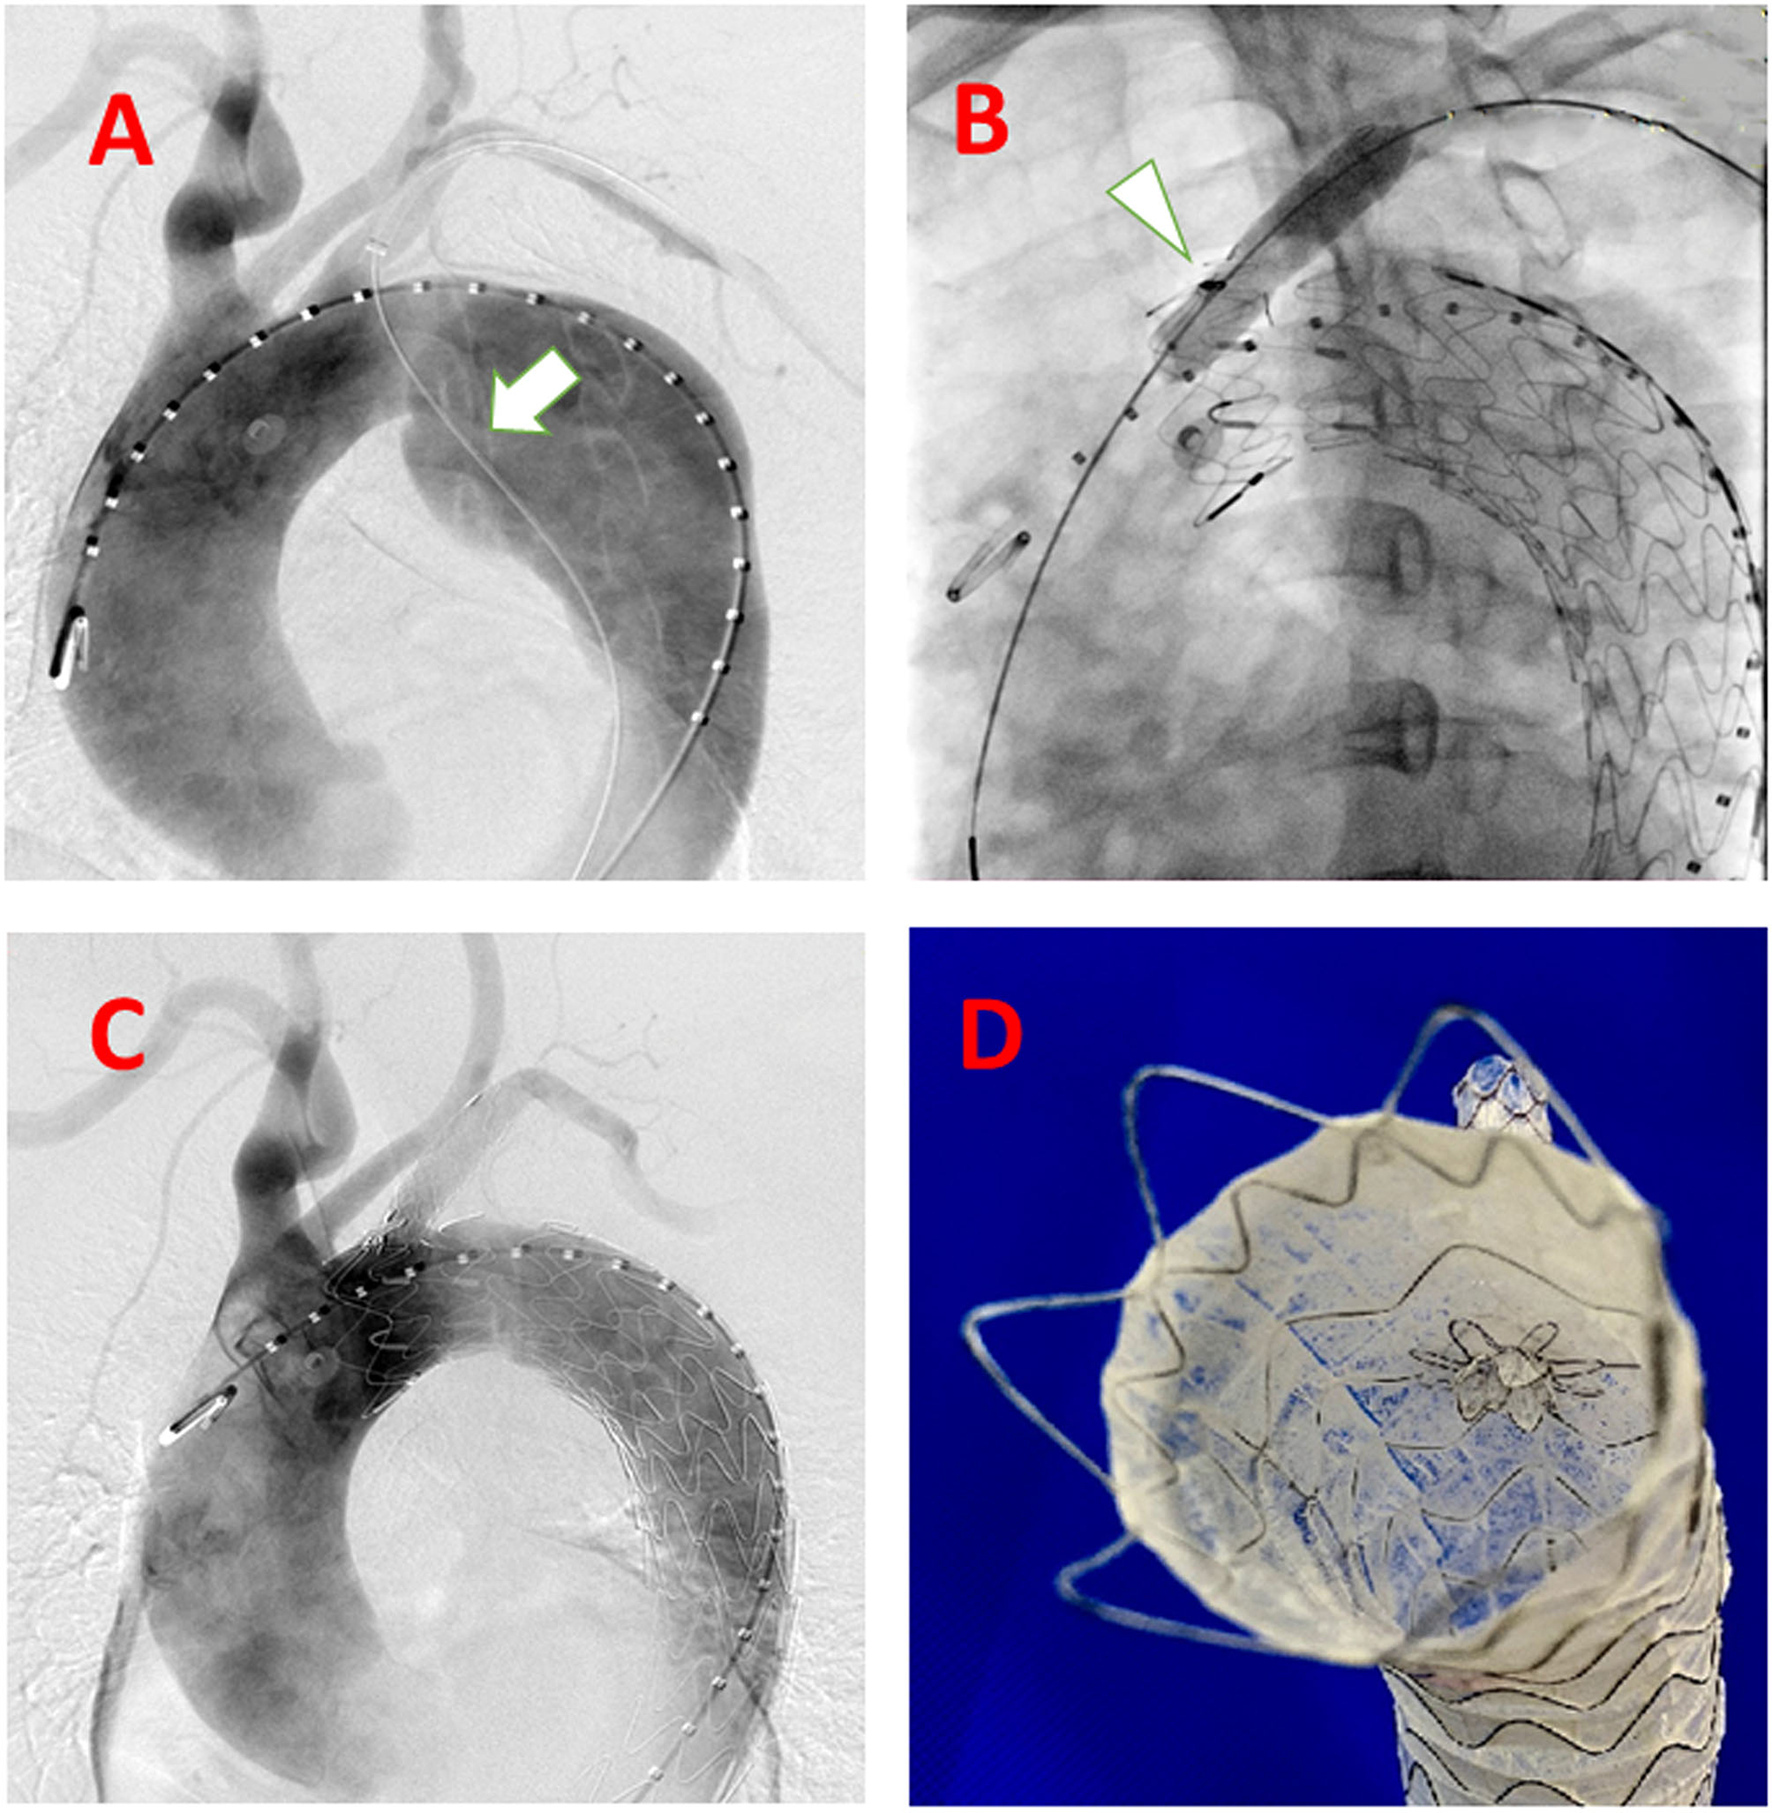

Figure 2

Steps of the system accomplished delivered in the human case. (A) guidewire (white arrow) from LSA to the descending aorta to the femoral artery as a strengthen wire, which makes puncture angle from LSA to aortic stent-graft more friendly; (B) After balloon expansion (white arrow) of the deployed C-skirt stent-graft; (C) DSA after the whole procedure accomplished; (D) Real view of the C-skirt stent-graft in the aortic stent graft.